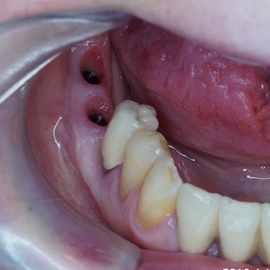

Odbudowa lewego dolnego trzonowca.

Odbudowa prawego dolnego trzonowca.

Odbudowa kości, dziąsła, implantacja, korony protetyczne, dwa prawe dolne trzonowce.